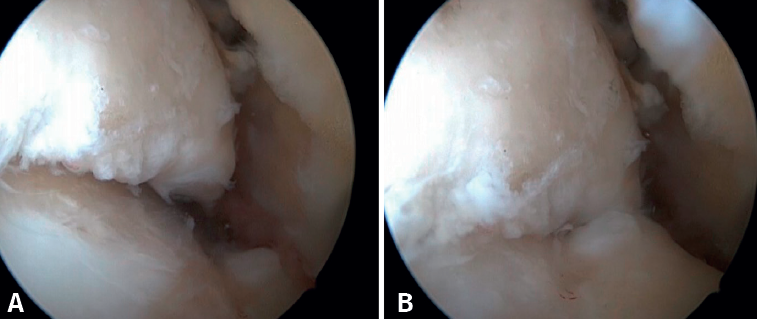

El PAT óseo por osteofitos también ha sido relacionado con la presencia de inestabilidad crónica. Se ha postulado que la alteración en la cinemática articular secundaria a la insuficiencia ligamentosa favorece el desarrollo de osteofitos en la región anterior de la tibia y el astrágalo(36,37). Estudios recientes han cuestionado la teoría de tracción capsular repetida como origen de los osteofitos en la práctica deportiva(38), ya que es fácilmente demostrable que los osteofitos se localizan intraarticulares por dentro de la inserción capsular, en el contexto de una artroscopia de tobillo (Figura 2). Por ello, la artroscopia con dorsiflexión de tobillo es fundamental para poder resecar los osteofitos de forma segura sin daño capsular ni a las estructuras suprayacentes, mientras que la técnica clásica de tracción (invasiva o no) dificultaría enormemente su resección, por lo que hoy en día se desaconseja su uso rutinario(3,39). Vega distingue dos tipos de osteofitos(3), según sean por trauma repetitivo (forma de pico) o por inestabilidad (en forma de visera). El concepto de microinestabilidad se asocia a microtraumatismos de repetición que podrían ser el origen de osteofitos con esta morfología característica (Figura 3).

Figura 2. Osteofito anterior de la tibia. A: en dorsiflexión la cápsula se separa del osteofito permitiendo su resección (B) mediante fresado.

Figura 3. Osteofito por inestabilidad crónica. A: el osteofito conforma un tope óseo que se extiende en el borde anterior del plafón tibial y la cara anterior del maléolo medial; B: imagen artroscópica.